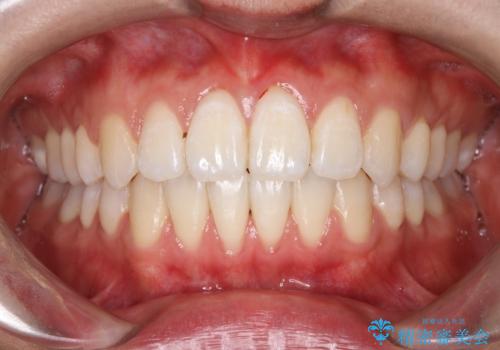

【ワイヤー矯正】前歯の突出感、下の歯の並びを良くしたい

- 主訴:上の前歯の突出感と下の歯の並びを改善したい

非抜歯にて矯正治療を行いました。

IPRを行い、前歯部の突出感の改善に努めました。

期間:1年9カ月